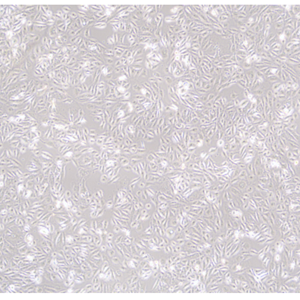

Caki-2 (人乳头状肾细胞癌细胞)